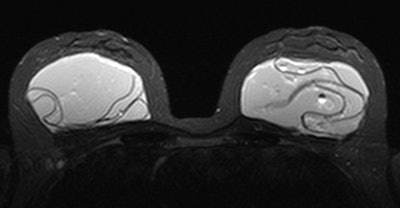

A prospective cohort study out of the Netherlands included 107 women with 214 PIP silicone implants who underwent explantation preceded by short-tau inversion recovery (STIR) MRI. Most of the patients were asymptomatic (70%), and all patients had not previously visited a doctor -- the women wouldn't have been seen if it weren't for the recall, according to Marike Maijers, a doctoral student and resident in plastic surgery at VU University Medical Center in Amsterdam. Maijers wrote her thesis on safety in the imaging of silicone breast implants, with a particular focus on PIP implants.

Nearly 75% (158) of the implants were correctly diagnosed as intact and 40 as ruptured. Sensitivity was 93%, specificity was 93%, positive predictive value was 77%, and negative predictive value was 98%. Interobserver agreement was excellent, with a kappa value of 0.92.